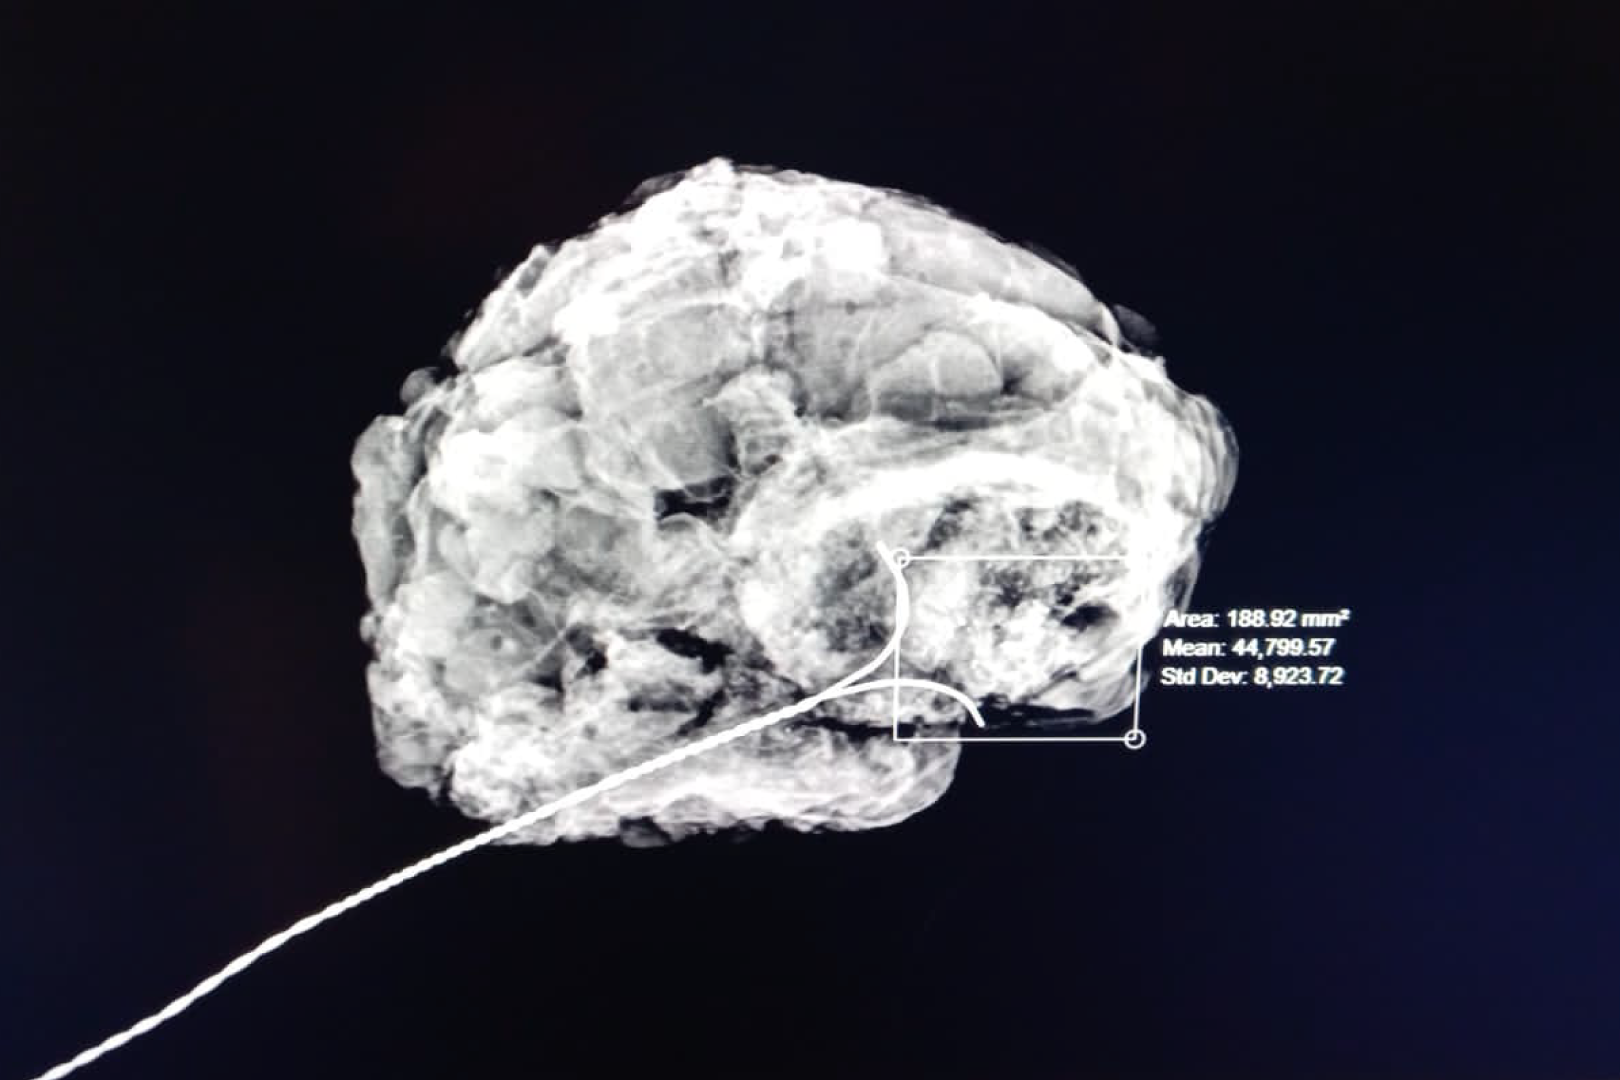

HD Live quinta dimensión, Imágenes de volumen con profundidad y claridad, que aportan un realismo anatómico para un mejor diagnóstico.